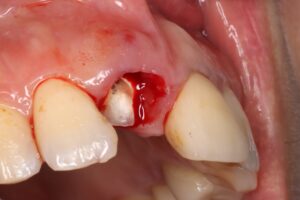

4、歯周外科処置を行って歯肉を切除して下げた状態。(図4の状態)

5、ファイバー樹脂の土台を入れて歯を補強した状態。(図5の状態)